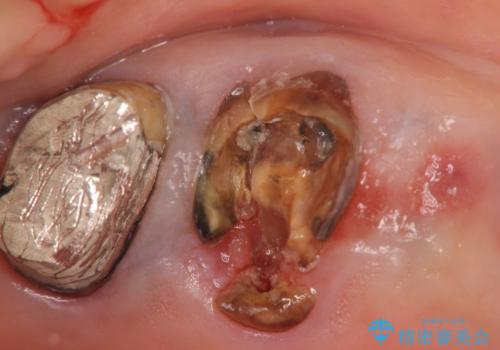

X線写真検査を行ったところ、ブリッジ支台の歯が破折(割れている状態)し抜歯が必要な状態です。

抜歯をしたのちしっかりと咬合力を回復し前後の歯を守るためにも、入れ歯やブリッジではなくインプラントによる咬合機能回復を計画します。

- 125.4万円(インプラント×2・チタンカスタムアバットメント×2・ジルコニアクラウン×4・仮歯×4)費用は治療当時の料金となります